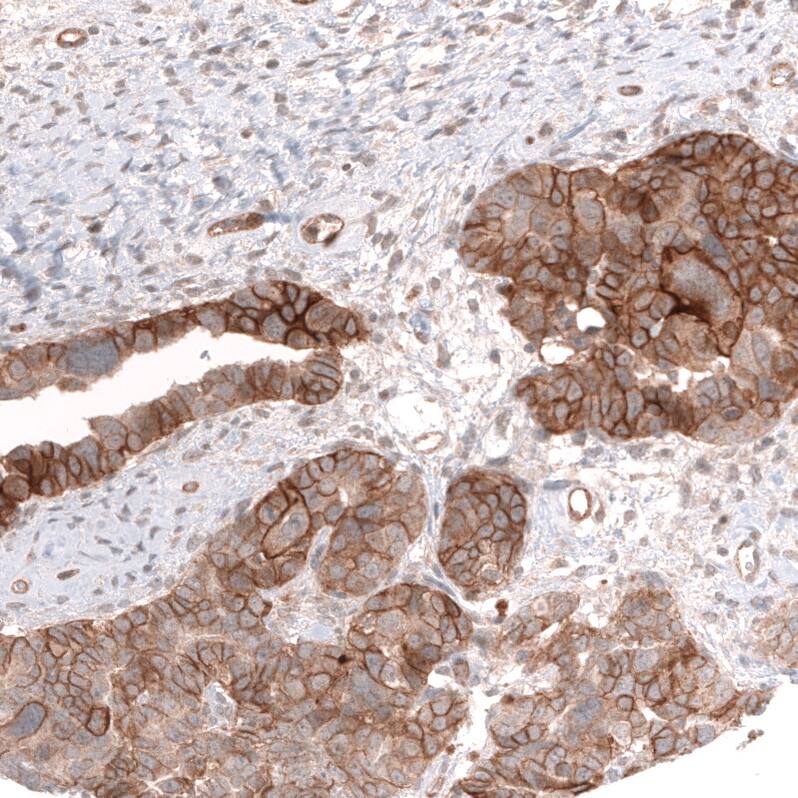

FXYD5/Dysadherin Antibody (CL14037) - Azide and BSA Free Immunohistochemistry-Paraffin: FXYD5/Dysadherin Antibody [NBP3-43835]

Immunohistochemistry-Paraffin: FXYD5/Dysadherin Antibody [NBP3-43835]

Staining of human breast cancer shows strong membranous positivity in tumor cells.